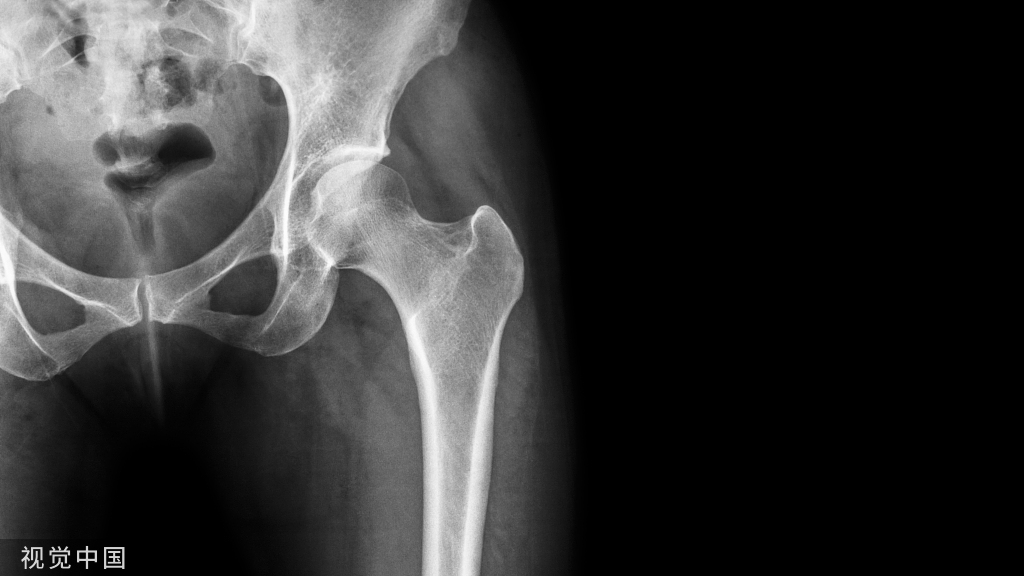

摔倒或车祸后髋部疼痛的患者急诊经常可见,临床医生会常规给他们行影像学检查如骨盆前后位、髋关节正侧位 X 线片等,明确是否存在骨折。

对于这类患者的 X 线片,需仔细观察:① 双侧股骨头及关节间隙的对称性② 髋臼及泪滴的完整性③ 4 个重要骨性标志的连续性:代表前柱的髂耻线、代表后柱的髂坐线、髋臼前缘和髋臼后缘

尽管仔细检查和评估,仍有一些外伤后髋部疼痛的患者,存在 X 片上难以发现的隐匿性髋部骨折。这种情况下,可以选择对骨髓水肿高度敏感的 MRI 进行随访(图 1)。

图 1 长跑运动员股骨隐匿性、应力性骨折。A 为髋部正位 片,虽未见明显骨折,但股骨颈基底部可见一模糊的线性硬化带(箭头)B 为 MRI 冠状位 STIR 序列扫描,示股骨颈应力侧可见一线性低密度信号影,周围包绕骨髓水肿的高密度影

从这个案例来看,长期运动的患者,如果出现髋部疼痛,X 线即使无特殊表现,也应考虑应力性骨折的可能性。

股骨近端骨折

股骨颈骨折常发生在老年人,头下型骨折最常见,但是当股骨外旋或有明显的关节炎骨赘形成时,骨折较难发现。此外,肥胖和骨量减少增加髋部 X 片诊断难度,所以需格外注意。

因骨结构重叠影响,股骨转子骨折发生轻度移位时亦很难发现,加做一个不同角度的 X 线片有助于诊断(图 7)。

图 7 摔倒后股骨大转子骨折。A 正位片初步检查未发现明显骨折,进一步检查发现大转子上方皮质中断(箭头)。B 蛙式侧位片示骨折分离,尤其是后方(箭头)。初步检查时忽视了这一点,是因为股骨颈未能充分显示

股骨颈应力性骨折

股骨颈应力性骨折在参加耐力运动的运动员中常见,且常发生在股骨颈压力侧。股骨颈基底部发现一垂直于骨皮质的线性硬化带可诊断这种类型的疲劳性骨折(图 8)。

图 8 长跑运动员股骨颈应力性骨折。X 片(A)和冠状位 CT 多维重建(B)图像示穿过股骨颈内侧皮质中的透亮区(箭头),周围硬化。骨折垂直于皮质

股骨颈张力侧的应力性骨折有可能发展为完全骨折(图 9)。

图 9 进食障碍患者股骨颈应力性骨折的张力侧。A 正位片示股骨颈完全骨折。B 2 周前的 X 片示局部骨量减少,正是后来发生骨折的位置(箭头)

非典型股骨骨折

另一种易漏诊的骨折是非典型股骨骨折,这种骨折与长期服用双膦酸盐相关,常发生在使用双膦酸盐 3 年以上的患者。前驱症状表现为腹股沟痛或大腿痛的患者中,60%~70% 被错误地认为由腰背痛或髋关节炎引起。

这种骨折的一个典型表现为火山口状骨膜隆起及一横行透亮带。值得注意的是,超过 50% 的患者表现为股骨干完全骨折。由于 50%~60% 的患者会累及双侧,所以一旦一侧下肢确诊,需行对侧下肢检查。

图 10 老年患者长期服用双磷酸盐引起的骨折。A 髋部正位片,箭头所示,股骨外侧皮质存在横行透亮带。B 后续的股骨 X 线片示局灶性骨膜反应,以及此类骨折的特征性表现-火山口状骨膜隆起(箭头)。C MRI 冠状位 STIR 序列扫描示相应骨折平面的骨髓水肿表现